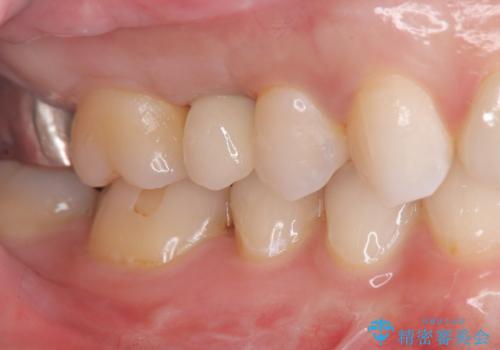

インプラント埋入手術は1回で全て行い、2ヶ月後にはセラミック治療で、審美回復と機能回復をしました。

来院回数が少なく、しっかり食事もできるとの事で非常に喜んで頂けました。